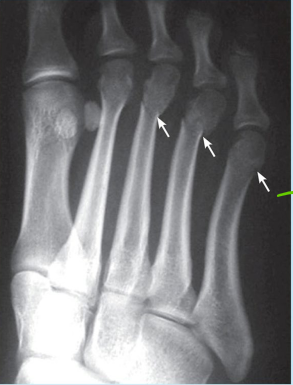

Q

Which bone is fractured? -potential situation in which fracture could occur

A

-3rd, 4th, and 5th metatarsals -Barbell on the Foot